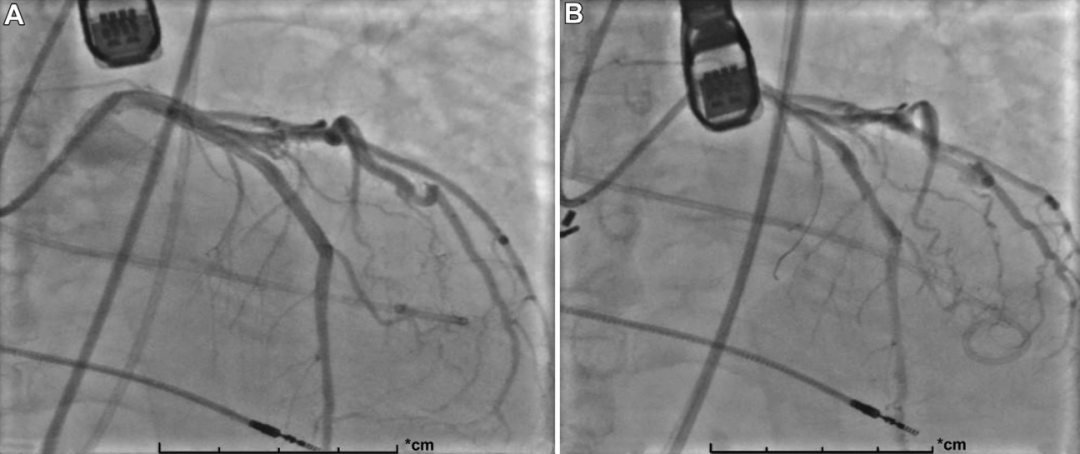

6F JL4导管管送至左主干,在造影和实时经食管超声心动图引导下,精确标测出第二间隔支供血至室间隔基底部。随后在5分钟内向目标间隔支注入酒精。术后造影确认目标间隔支成功闭塞(图4)。

图4 血管造影

(A)在经食管超声心动图引导下定位第二室间隔支;(B)ASA后血管造影证实注入酒精的间隔支成功闭塞。